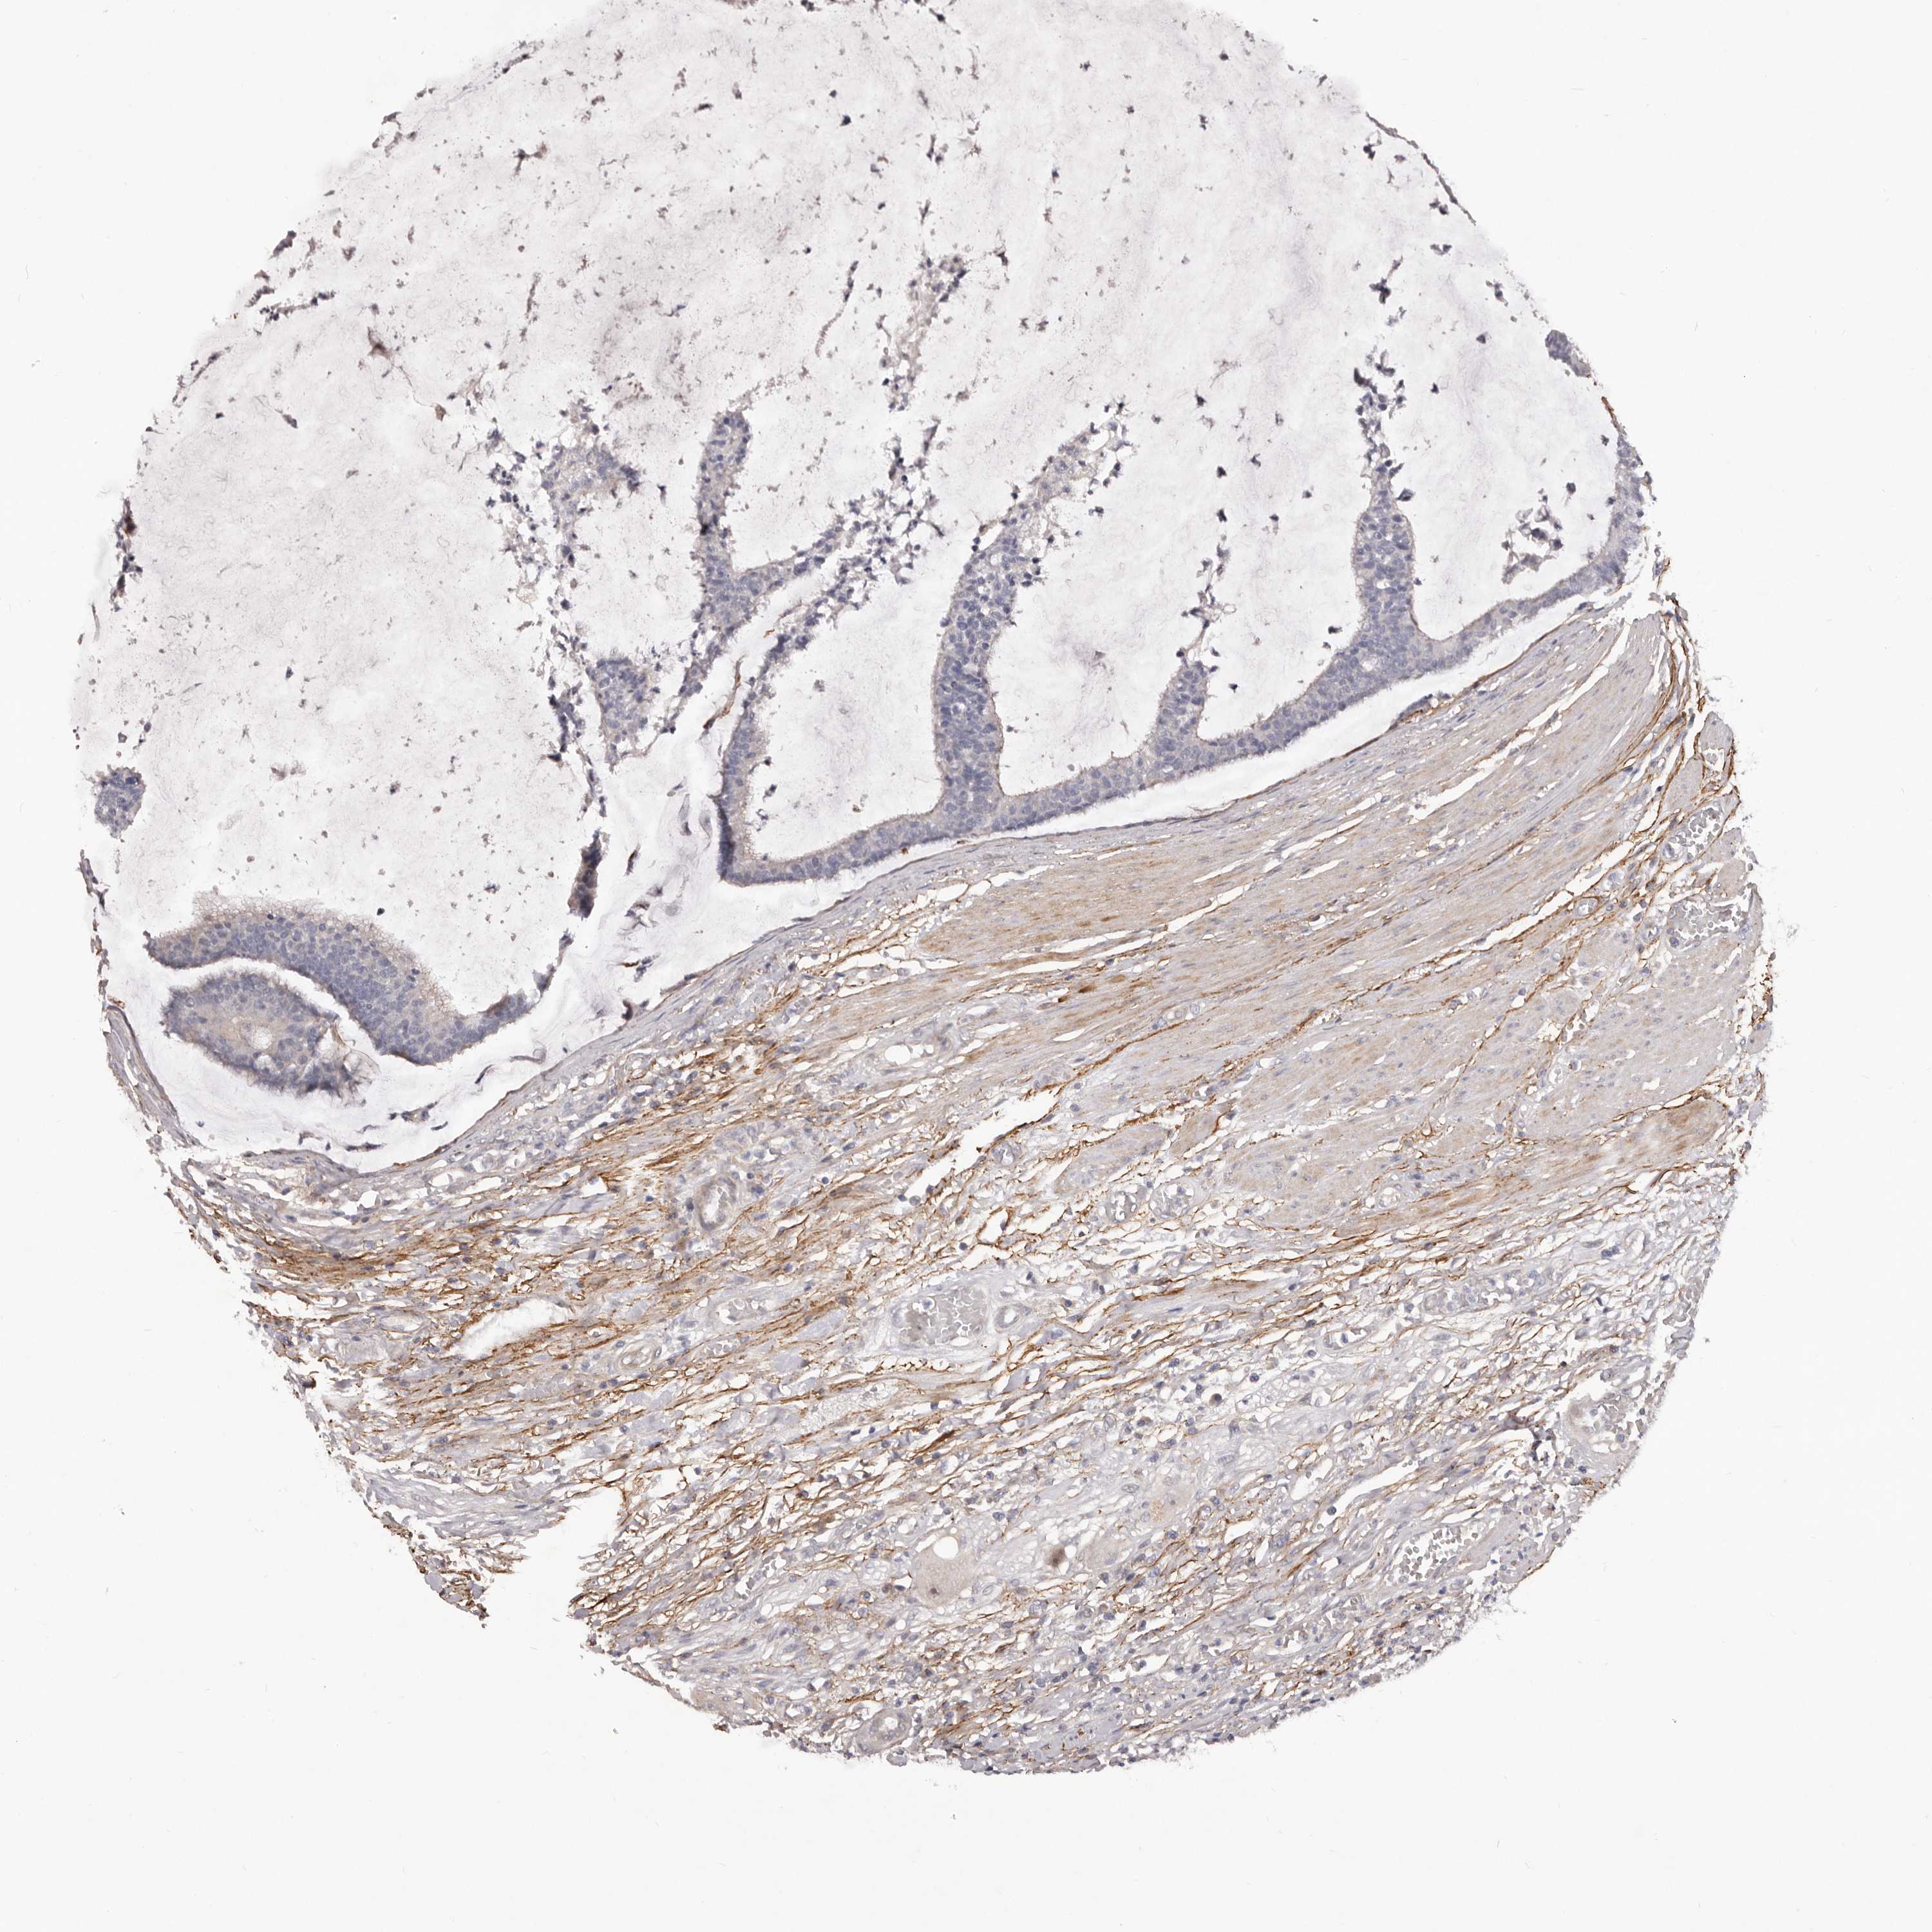

CANCER COLORECTAL CANCER Show tissue menu

Colorectal cancer

Human cancer

Colon adenocarcinoma